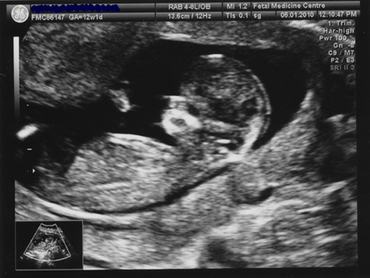

A vérvétel előtt aláírtam egy nyomtatványt arról, hogy hozzájárulok, hogy vizsgálatom eredményét a professzor kutatásaiban felhasználja és a világgal megossza. Mire az ultrahangos vizsgálóban lefekhettem, már szinte alig bírtam titkolni az idegességemet. Hirtelen minden félelmem előjött, eszembe jutottak a fórumos bejegyzések anyukáktól, akiknél a 12. heti ultrahangon nem találták a szívhangot (miért mindig az ilyenekre emlékszünk és nem arra a sok ezerre, ahol minden rendben találtatott?) Az járt a fejemben, hogy vajon nem ez-e a terhességem utolsó boldog perce? Remegő kézzel lejjebb húztam a nadrágomat, a szonográfus hölgy bekente a hasam meleg zselével, elkezdte tologatni rajta a ketyerét, és én ezalatt egyetlenegyszer nem vettem levegőt. Azután meghallottam a szívhangot, és hirtelen iszonyú boldogság töltött el. A vizsgálat alapos volt és nagyon hosszú, és a szonográfus végigkommentálta. Elmesélte, hogy nem könnyű mérnie, mert éppen görcsben van a méhem, ami teljesen normális, és akár 30 percet is eltarthat. Pontosan elmondta, hogy mit néz és mér éppen, és mindig hozzátette, hogy minden rendben lenni látszik. Az orrcsont, aminek hiánya baljós jel, tisztán látható volt. Amikor a tarkótáji vizenyőre irányította az ultrahangot, meredt szemmel követtem, és láttam, hogy hol van az a sötét terület, amit mér. Még egy laikus számára is láthatóan kicsi volt, egy hosszú, nagyon keskeny csík. mérések után bejött a professzor, akivel a szonográfus megosztotta az adataimat. A professzor mosolyogva kezet rázott velem, megsimogatta a lányunk arcát, és elfoglalta a helyet a gép előtt. Úgy tűnt, hogy megismételte és ellenőrizte a mérések egy részét, és ő is végig beszélt hozzánk. Bár nyilván tízezredszer osztott meg jó eredményt kismamával, egy percre sem éreztem azt, hogy rutineset vagyok. Segített felülni és megmutatott egy felfelé ívelő görbét a képernyőjén. "A kora alapján ennyi lenne az esélye genetikai rendellenességre" mutatta a görbén. "Az ultrahang és a vérvizsgálat alapján pedig ennyi", mutatott a görbe ellenkező oldalára. "Pontosan annyi, mint egy 15 éves lánynak. Szokott úgy viselkedni, mint egy 15 éves lány?", kérdezte kuncogva a páromtól. A pasik összemosolyogtak, én felöltöztem és egy kicsit még mindig remegve felálltam. Kaptunk egy papírt tele számokkal és táblázatokkal, továbbá egy végszóval arról, hogy nem ajánlanak semmiféle további tesztet a rizikófaktorom alapján.

Kisétáltunk a hóesésbe. Hazáig mosolyogtam, és a metrón párpercenként megnéztem a homályos fényképeimet. Nem arra gondoltam, hogy "mi lett volna, ha...", ez a gondolat csak azoknak a fejében jár, akikkel valami rossz történik. A kiváltságosok nem kérdezik a sorstól, hogy "Miért ÉN?" Ezeket a kérdéseket remélem soha nem kell feltennem egy vizsgálaton. Mint ahogy még mindig nem tudom, hogy én hogyan döntenék, ha nem nyertem volna a genetikai lottón. Ami egyébként akkor is csoda jó érzés, ha 99,5 százalék, hogy kihúzzák a számaidat.